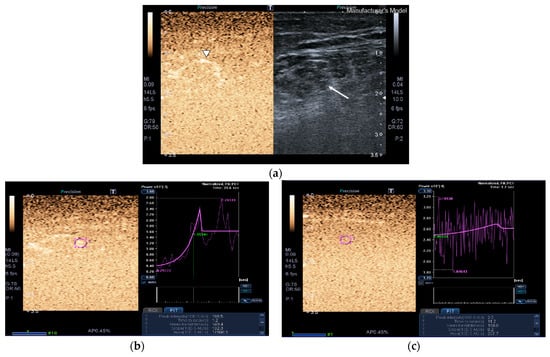

SWE images of a case and a healthy control are shown in Figure 1.

Quadriceps rectus femoris (QRF) muscle ultrasound (US) scan and shear wave elastography (SWE) with several regions of interest (ROIs) (pink circles) measured across the muscle of a matched healthy control (63 years old). SWE shows high muscle elasticity. (a) Transversal QRF muscle (arrow) US scan, femur (arrowhead); (b) longitudinal QRF muscle (arrow) US scan, femur (arrowhead). Patient with multiorgan failure (67 years old). SWE shows muscle stiffness with several regions of interest (ROIs) (pink circles). (c) Transversal QRF muscle (arrow) US scan, femur (arrowhead); (d) longitudinal QRF muscle (arrow) US scan, femur (arrowhead).